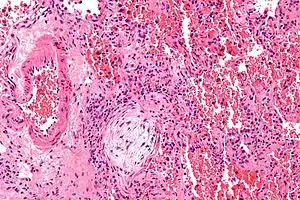

| Micrograph showing a Masson body (off center left/bottom of the image – pale circular and paucicellular), as may be seen in cryptogenic organizing pneumonia. The Masson body plugs the airway. The artery associated with the obliterated airway is also seen (far left of the image). H&E stain. | |

Organizing pneumonia is usually preceded by some type of lung injury that causes a localized denudation or disruption in continuity of the epithelial basal laminae of the type 1 alveolar pneumocytes that line the alveoli.[9] This injury to the epithelial basal lamina results in inflammatory cells and plasma proteins leaking into the alveolar space and forming fibrin, resulting in an initial fibroblast driven intra-alveolar fibroproliferation.[9] The fibroblasts differentiate into myofibroblasts and continue to form fibrosis resulting in intra-alveolar fibroinflammatory buds (Masson's Bodies) that are characteristic of organizing pneumonia.[9] These Masson's bodies consist of inflammatory cells contained in an extracellular matrix consisting of type I collagen, fibronectin, procollagen type III, tenascin C and proteoglycans.[9] Angiogenesis , or the formation of blood vessels, occurs in the Masson's bodies and this is driven by vascular endothelial growth factor.[9] Remodeling occurs, resulting in the intra-alveolar fibroinflammatory buds (Masson's Bodies) moving into the interstitial space and forming collagen globules that are then covered by type 1 alveolar epithelial cells with well developed basement membranes. These type 1 alveolar epithelial cells (pneumocytes) then proliferate, restoring the continuity and function of the alveolar unit.[9] This process is in contrast to the histopathologic changes seen in usual interstitial pneumonia where extensive fibrosis and inflammation occur leading to fibroblastic foci to form in the alveolar spaces resulting in obliteration of the alveolar space, scarring and significant damage to lung architecture (the alveoli).[9]

Biopsy findings in patients with organizing pneumonia consist of loose connective tissue plugs involving the alveoli, alveolar ducts and bronchioles. The loose connective tissue plugs occupying the alveolar spaces often connect to other connective tissue plugs in nearby alveoli via the pores of Kohn creating a characteristic butterfly pattern on histology.[9] There is usually minimal to no interstitial inflammatory changes in biopsies of organizing pneumonia.[9]

Histologically, cryptogenic organizing pneumonia is characterized by the presence of polypoid plugs of loose organizing connective tissue (Masson bodies) within alveolar ducts, alveoli, and bronchioles.